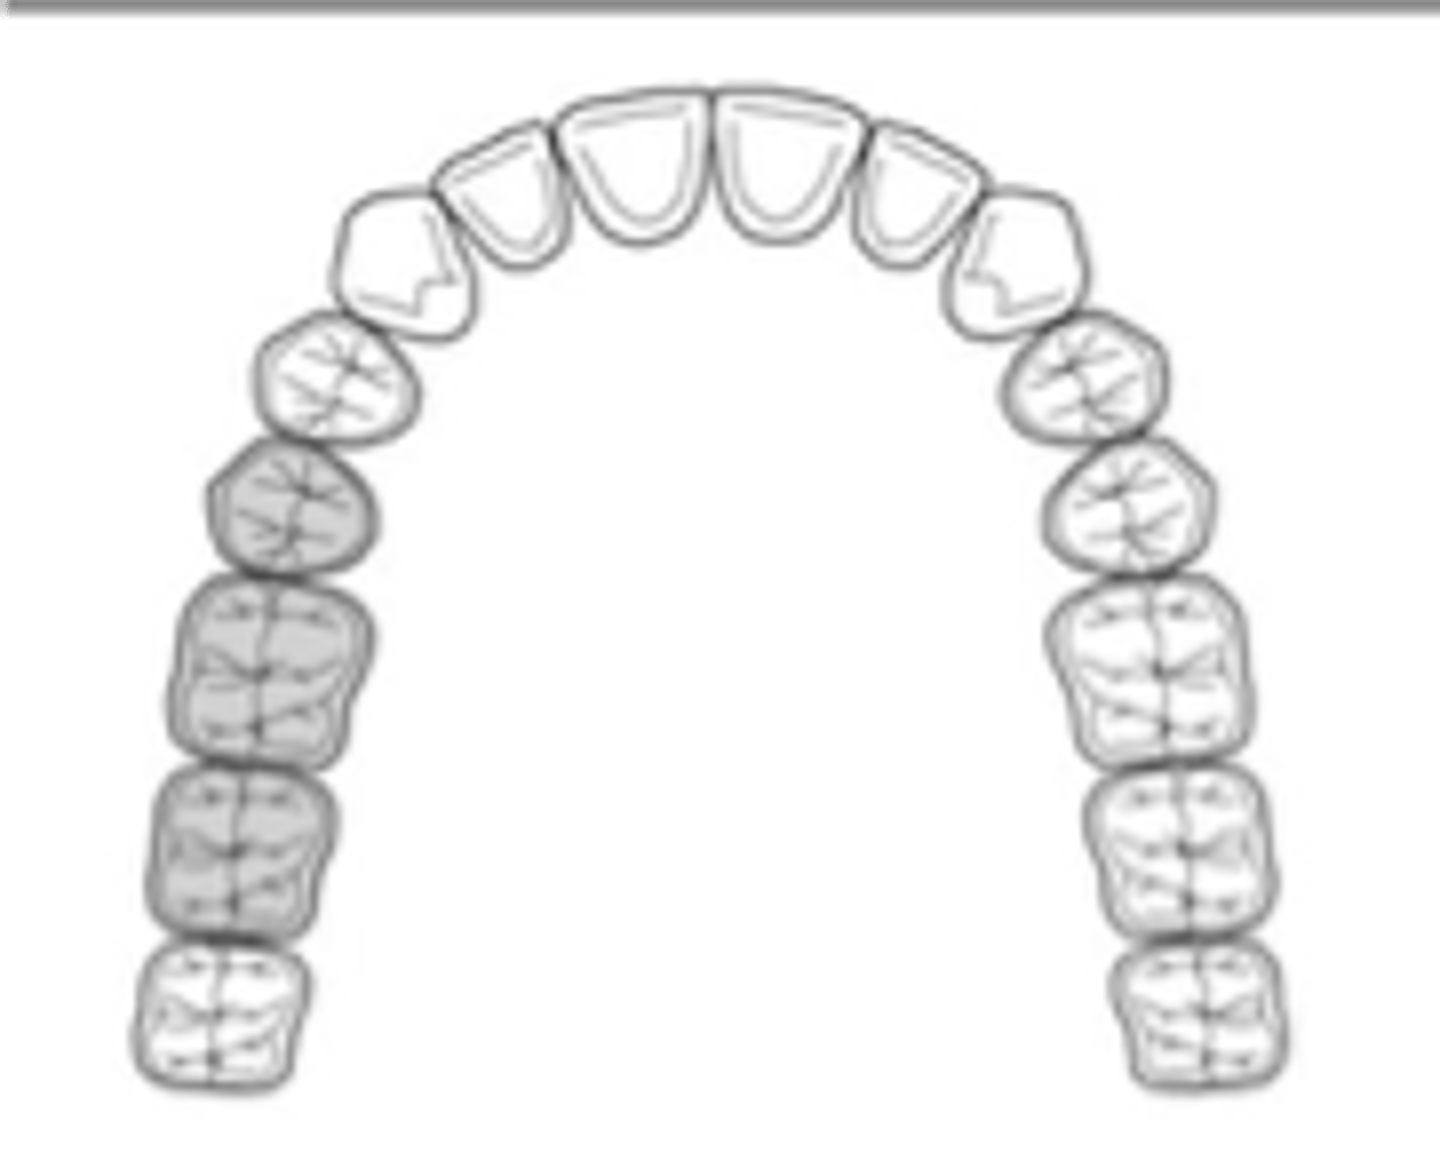

Kennedy Class I

Tooth and tissue supported:

bilateral edentulous area posterior to natural teeth

N/A - complete denture

which Kennedy Class?